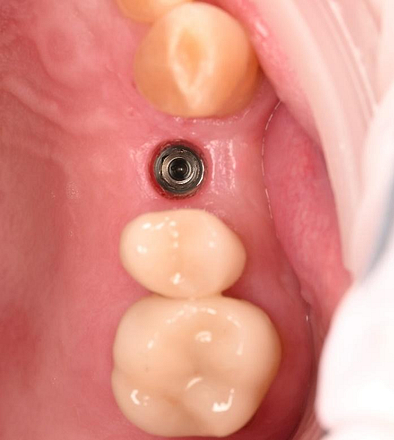

Three months after the implant surgery, a thorough post-operative assessment revealed excellent healing and implant stability.

Digital impressions were captured using the TRIOS 4 intraoral scanner, and the implant-supported crown was designed using 3Shape Design Studio.